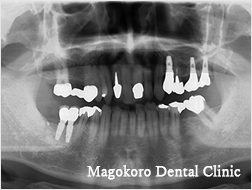

インプラント義歯

インプラントの上に磁石のアタッチメントをつけ、その上に取り外し式の義歯をつける方法です。

通常の義歯のように口の中で動くことがなく、より強く咬むことができます。インプラントブリッジに比べ、少ない本数のインプラントで治療することが可能です。

症例は上顎に3本のインプラントを入れ、磁石付の義歯を入れた患者様です。